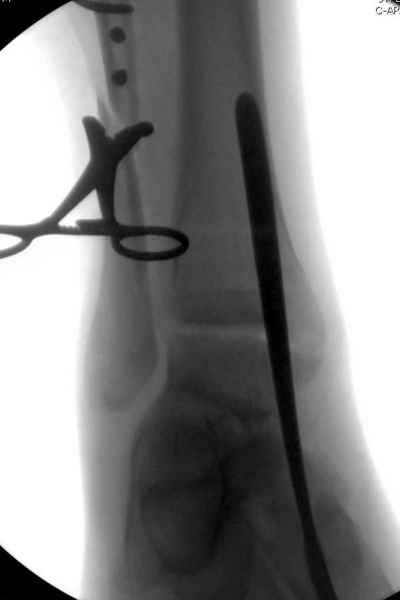

Здесь похожий случай трехнедельной давности, перелом почти сросся и была укорочена малоберцовая, на операции длину малоберцовой смогли восстановить только после того, когда проксимальнее пластины ввели шуруп и использовали его как толкатель, с помощбю дистракционого инструмента (lamina spreader).

Меньше всего волнует положение медиальной лодыжки - в любое время можно провести остео или реостеосинтез, при несращении можно просто резецировать без ущерба для движений в голеностопе. Здесь обошлись фиксацией одним 4 мм канюлированным шурупом.